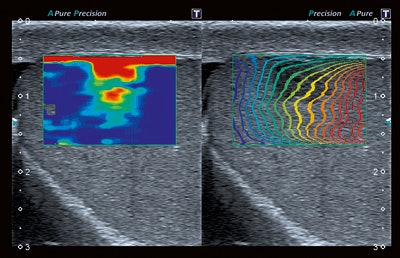

Meanwhile, Hitachi Medical Systems is launching two new members of its Arietta range of ultrasound platforms. Both the Arietta Precision and Prologue use the same core technology and electronics, but with an application-specific design for the housing. The former offers versatility for interventional and surgical procedures, the company states. Its transducer range covers minimally invasive investigations through to full open surgery, and it also has options for customized use in the operating room, with a large monitor that can be suspended from a wall or support arm and can be viewed from a distance.